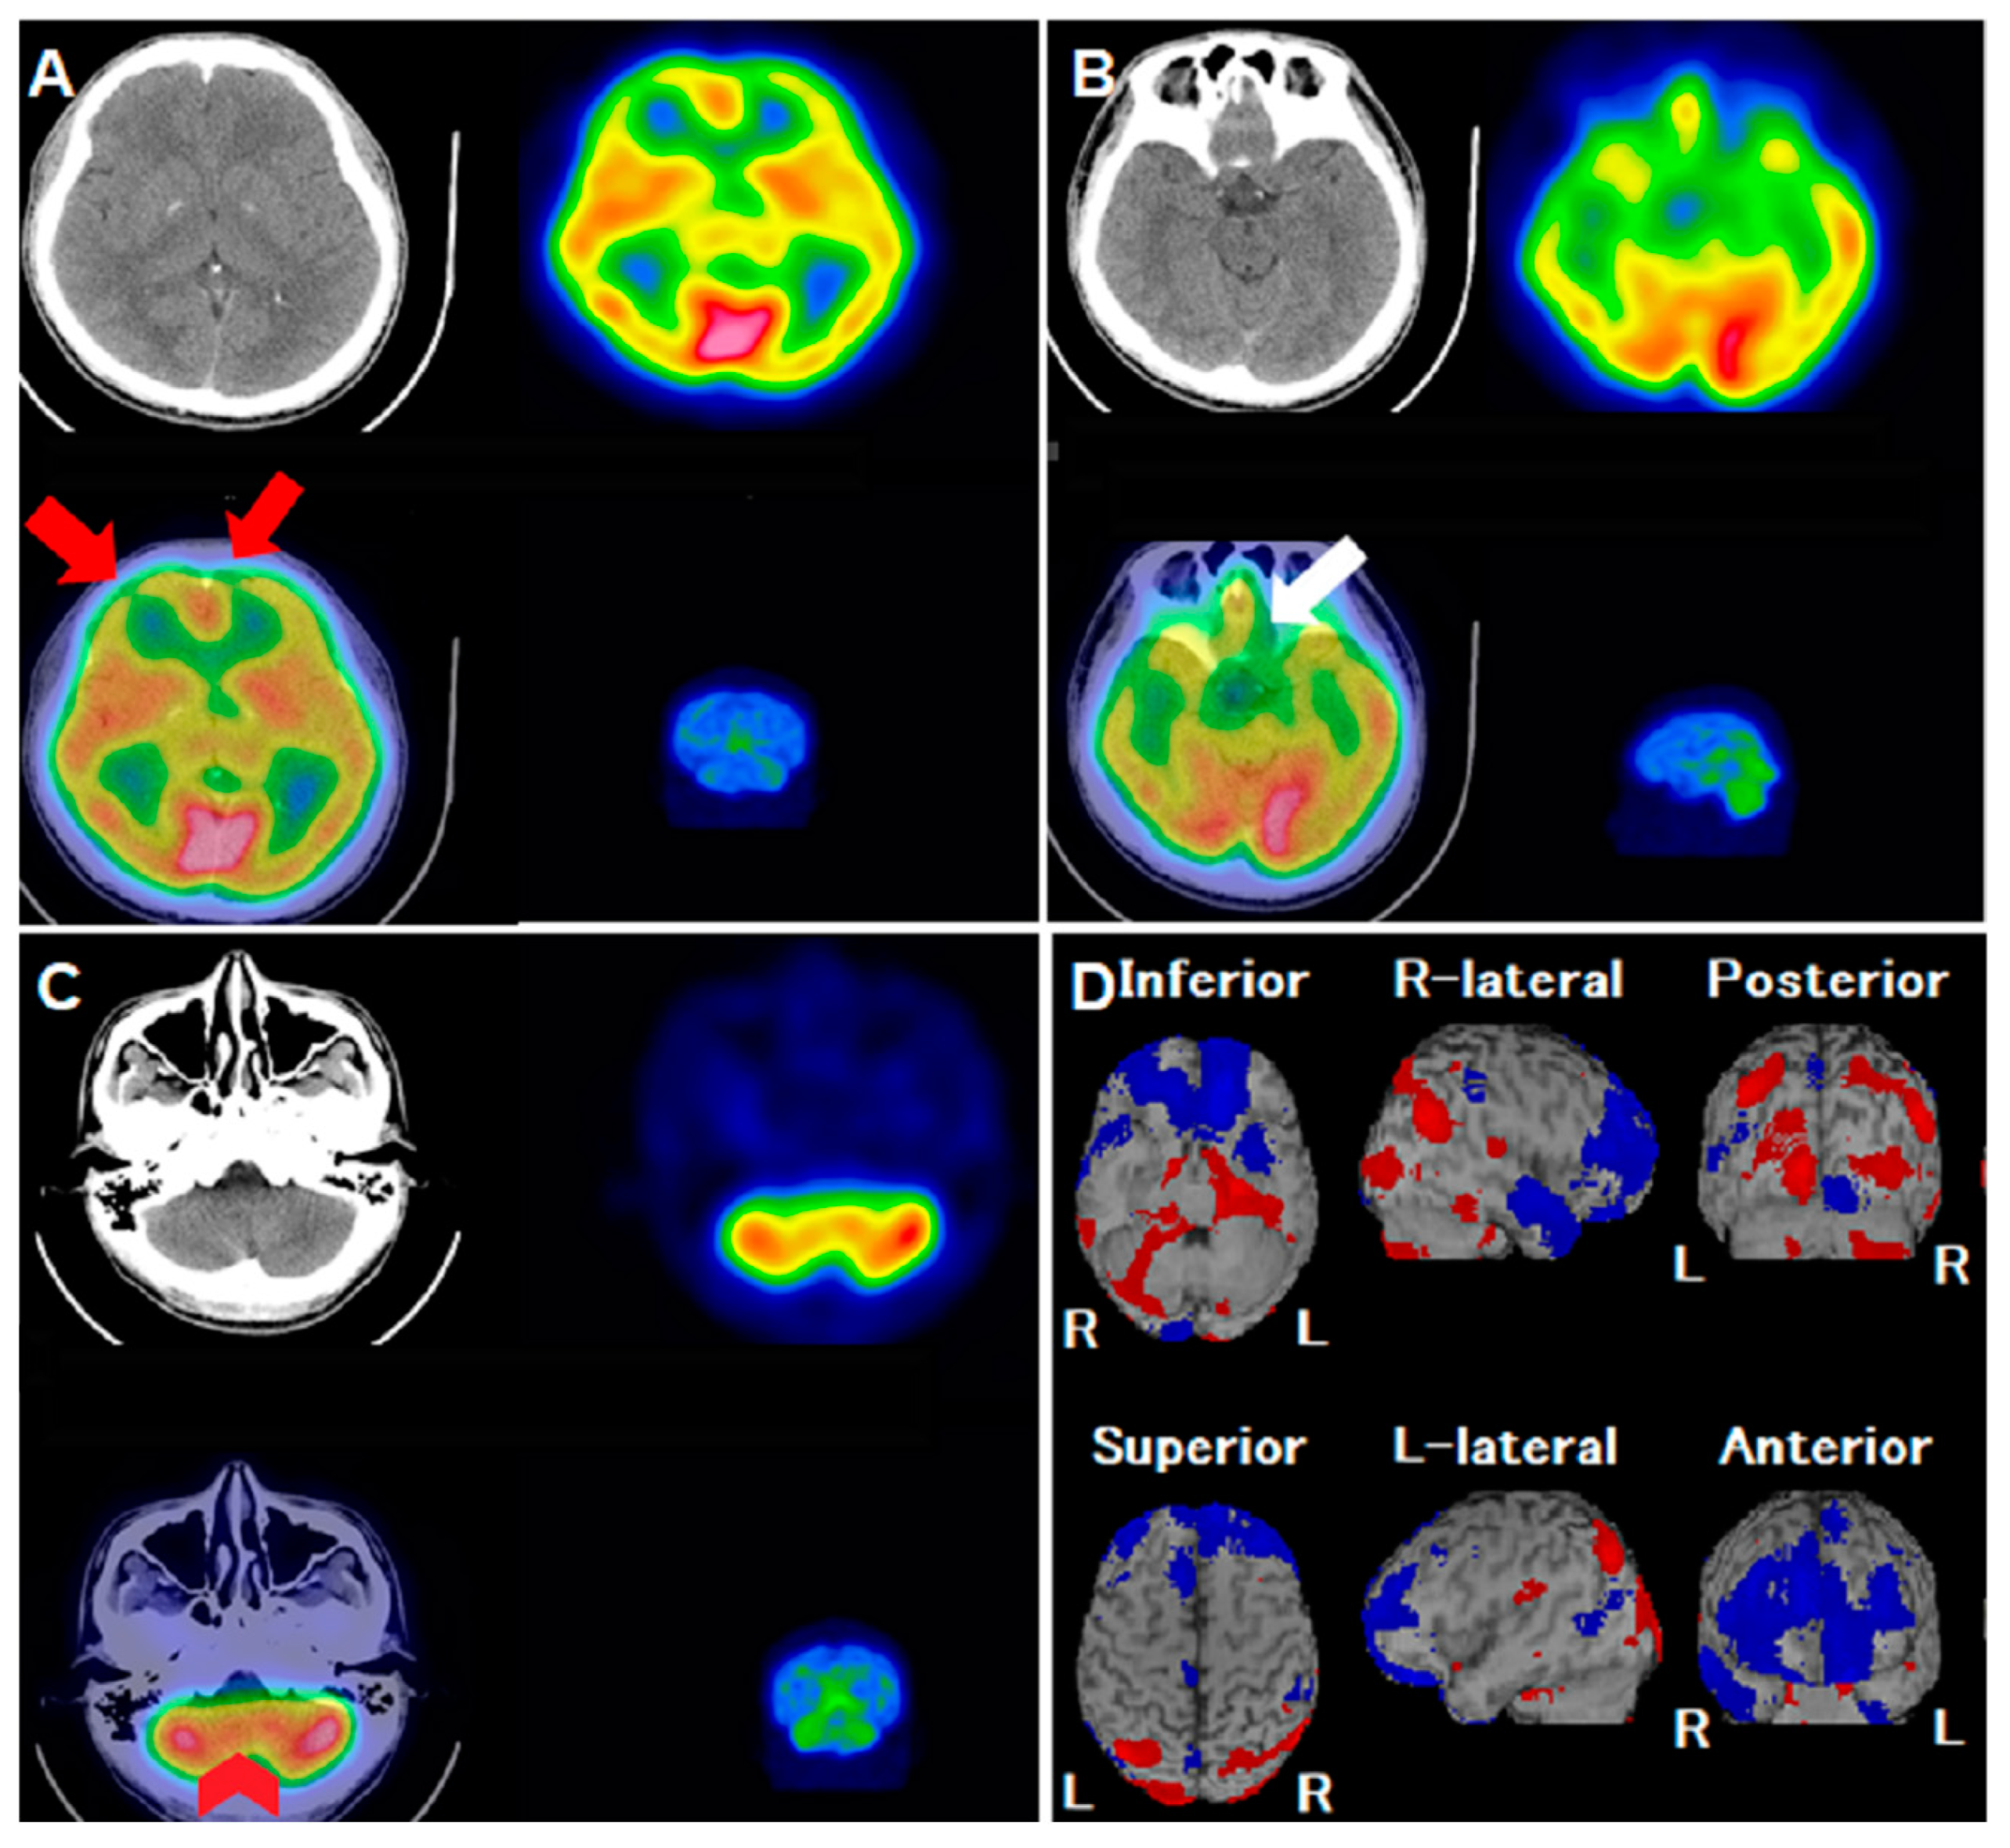

Abnormalities in Regional Cerebral Blood Flow Due to Headache in a COVID-19 Infected Patient Observed on 99mTC-ECD Brain SPECT/CT

Chu, Y.-C.; Chang, S.-T.; Chan, H.-Y.; Shen, D.H.-Y.; Chan, H.-P. Abnormalities in Regional Cerebral Blood Flow Due to Headache in a COVID-19 Infected Patient Observed on 99mTC-ECD Brain SPECT/CT. Reports 2023, 6, 58. https://doi.org/10.3390/reports6040058